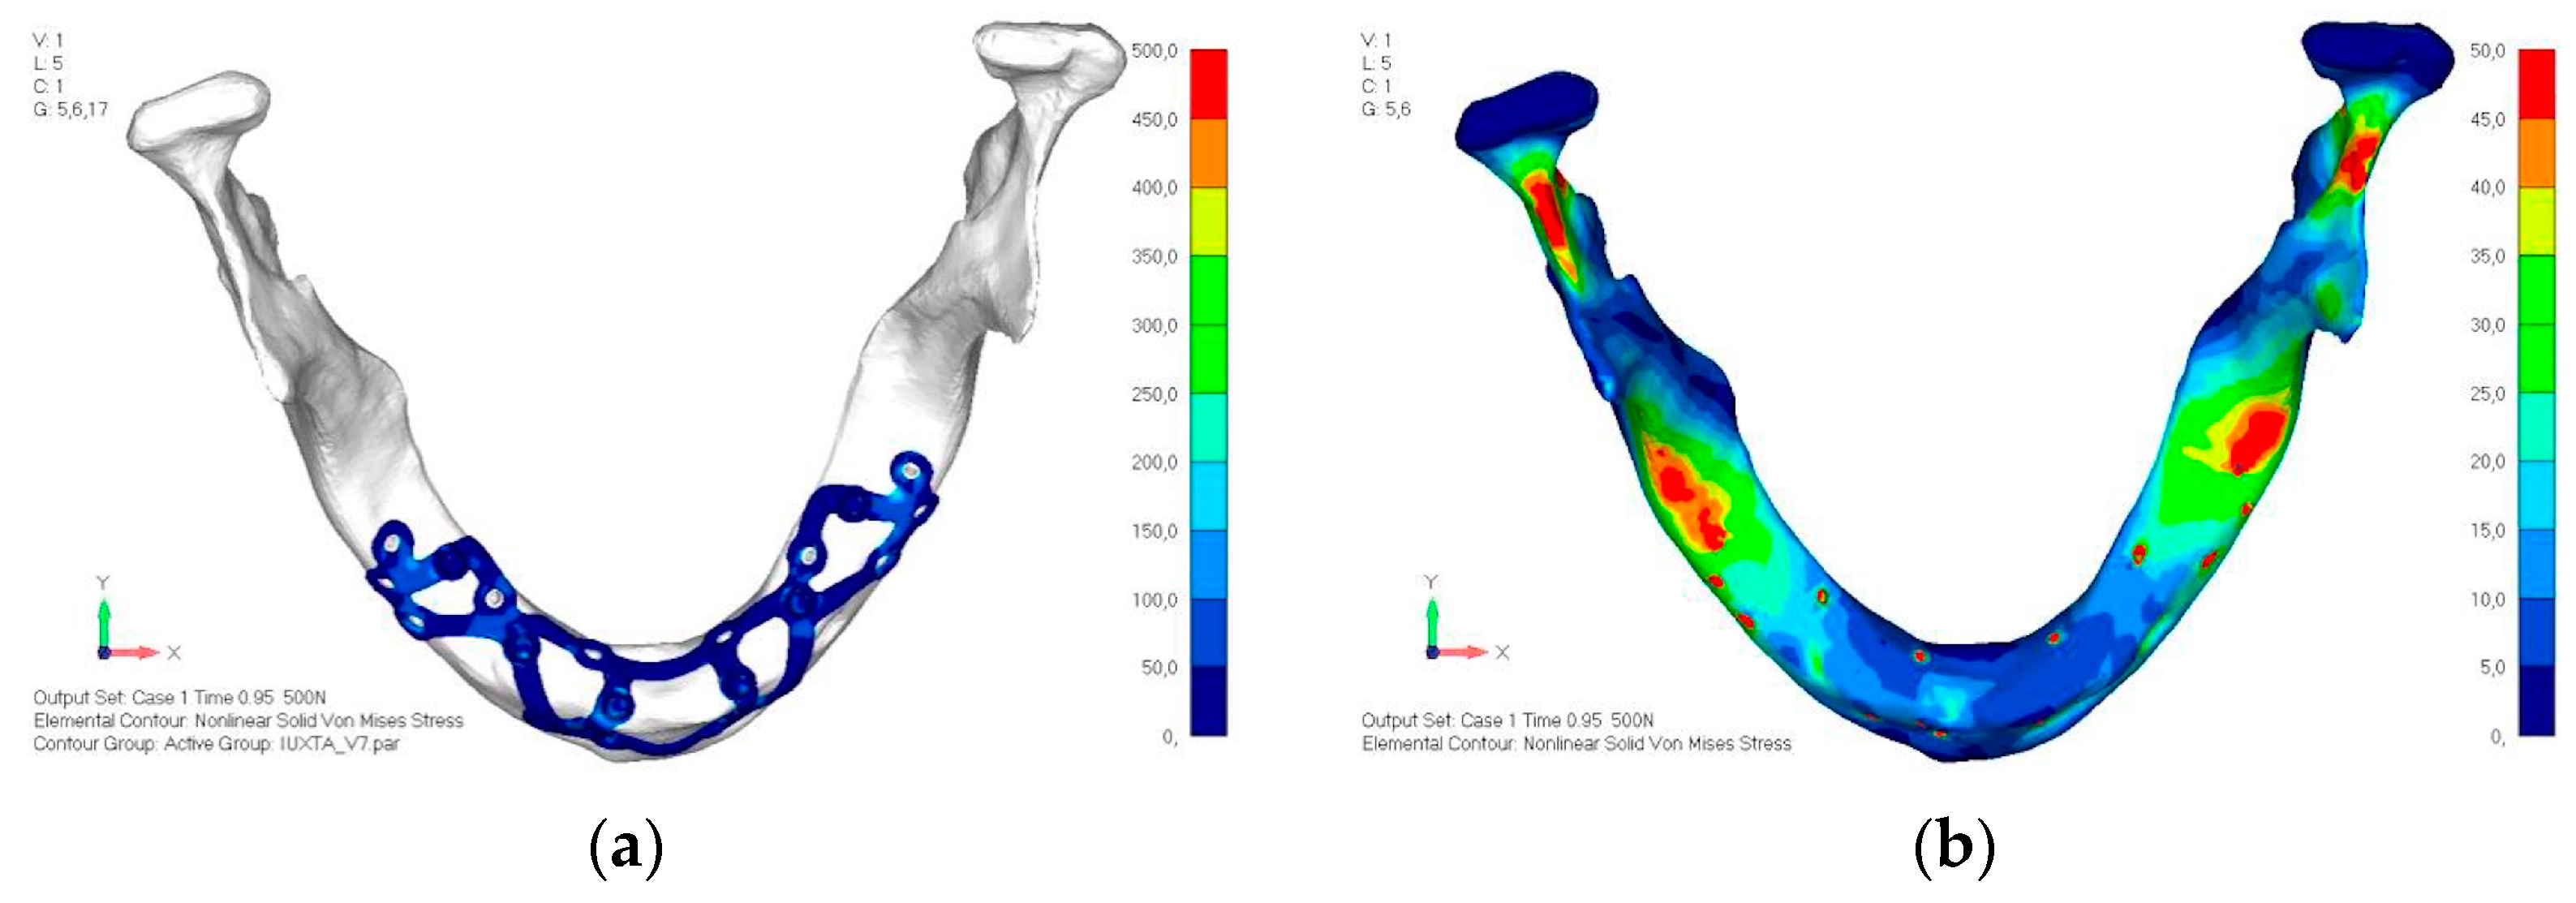

- Model V0. This model represents the initial analysis performed on the lower arch. The implant consists of two completely separate hemi-arches. The situation observed in the lower model is very similar to that found in the upper model. The most significant load is load 3 (Figure 20a,b), corresponding to chewing in the anterior right sector. Loads distributed over larger areas, such as configurations 1 and 2, result in less stress on both the implant and the bone (Figure 21 and Figure 22).

- Even in the lower model, the stresses observed in the peri-implant bone are always acceptable and significantly lower compared to those found in the upper implant. In the worst case, peak stresses reached 250 MPa, which ensures an adequate safety margin. From the bone perspective, in load configuration 3, it is noted that stresses exceed 50 MPa even in areas distant from the implant, such as near the condyles and in the posterior alveolar process.